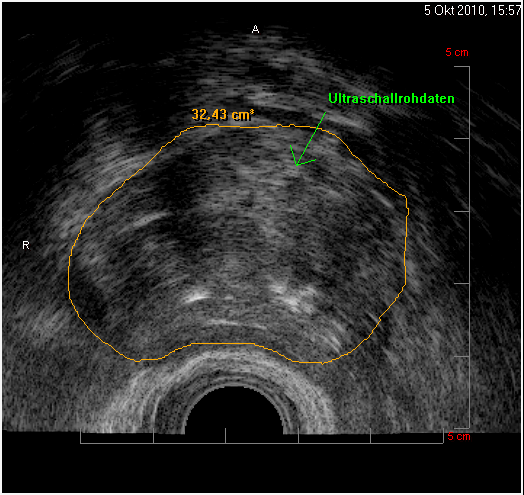

Die transurethrale Prostataresektion (TURP) galt viele Jahre als Methode der Wahl. Bei einer Prostatagröße von 30 bis 80 ml ist das nach wie vor eine gute Option. Dabei wird nur der unmittelbar um den Bereich der Harnröhre liegende Prostatabereich entfernt. Der Harnröhrenschließmuskel wird normalerweise geschont. Eine erneute Nachresektion ist selten nötig. Nicht so selten kommt es nach diesem Eingriff jedoch zu einer sogenannten retrograden Ejakulation, d.h., dass das Ejakulat beim Orgasmus nicht über die Harnröhre ausgestossen wird sondern direkt in die Harnblase.

Mittels Greenline-Laser lassen sich damit größere Prostatavolumina über 40 ml verkleinern. Nicht geeignet sich Patienten mit vorbestehender Bestrahlungstherapie der Prostata (bei Prostatakarzinom) oder nach Brachytherapie mittels Seeds. Patienten mit einer HIV oder Hepatitis-C-Infektion dürfen/sollten damit nicht behandelt werden. Warum? Weil ein infektiöser Dampf/Staub beim Verdampfen entsteht, der für das OP-Personal gefährlich sein könnte.